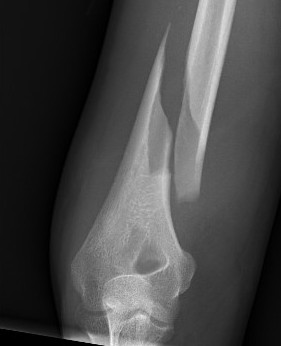

Holstein Lewis / distal humerus fracture